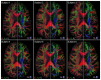

In diffusion tensor magnetic resonance imaging (DT-MRI), limitations concerning complex fiber architecture (when an image voxel contains fiber populations with more than one dominant orientation) are well-known. Fractional anisotropy (FA) values are lower in such areas because of a lower directionality of diffusion on the voxel-scale, which makes the interpretation of FA less straightforward. Moreover, the interpretation of the axial and radial diffusivities is far from trivial when there is more than one dominant fiber orientation within a voxel. In this work, using (i) theoretical considerations, (ii) simulations, and (iii) experimental data, it is demonstrated that the mean diffusivity (or the trace of the diffusion tensor) is lower in complex white matter configurations, compared with tissue where there is a single dominant fiber orientation within the voxel. We show that the magnitude of this reduction depends on various factors, including configurational and microstructural properties (e.g., the relative contributions of different fiber populations) and acquisition settings (e.g., the b-value). These results increase our understanding of the quantitative metrics obtained from DT-MRI and, in particular, the effect of the microstructural architecture on the mean diffusivity. More importantly, they reinforce the growing awareness that differences in DT-MRI metrics need to be interpreted cautiously.